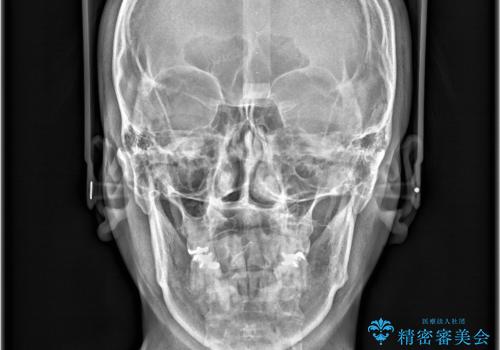

- 「歯のデコボコと前歯が引っ込んでいるのを治したい」を主訴に来院された患者様です。

デコボコの量が多かったため上下左右4を抜歯してワイヤー矯正で治療を行いました。

顔貌に対して歯の正中も合いました。